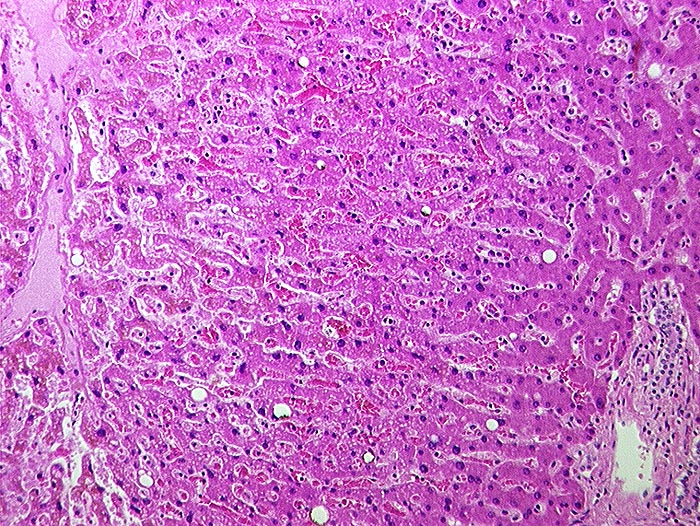

Subakute Stauung der Leber

Pathologischer Befund

Normalbefund